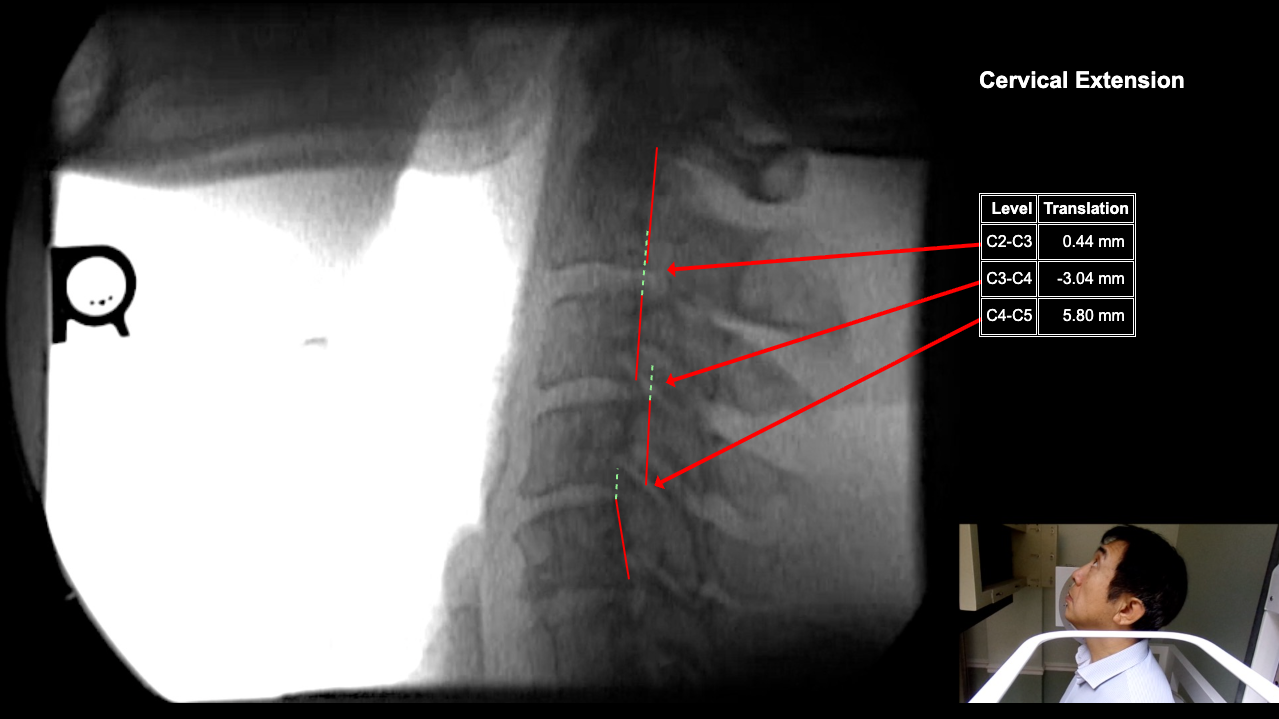

Image Name Image Type Image